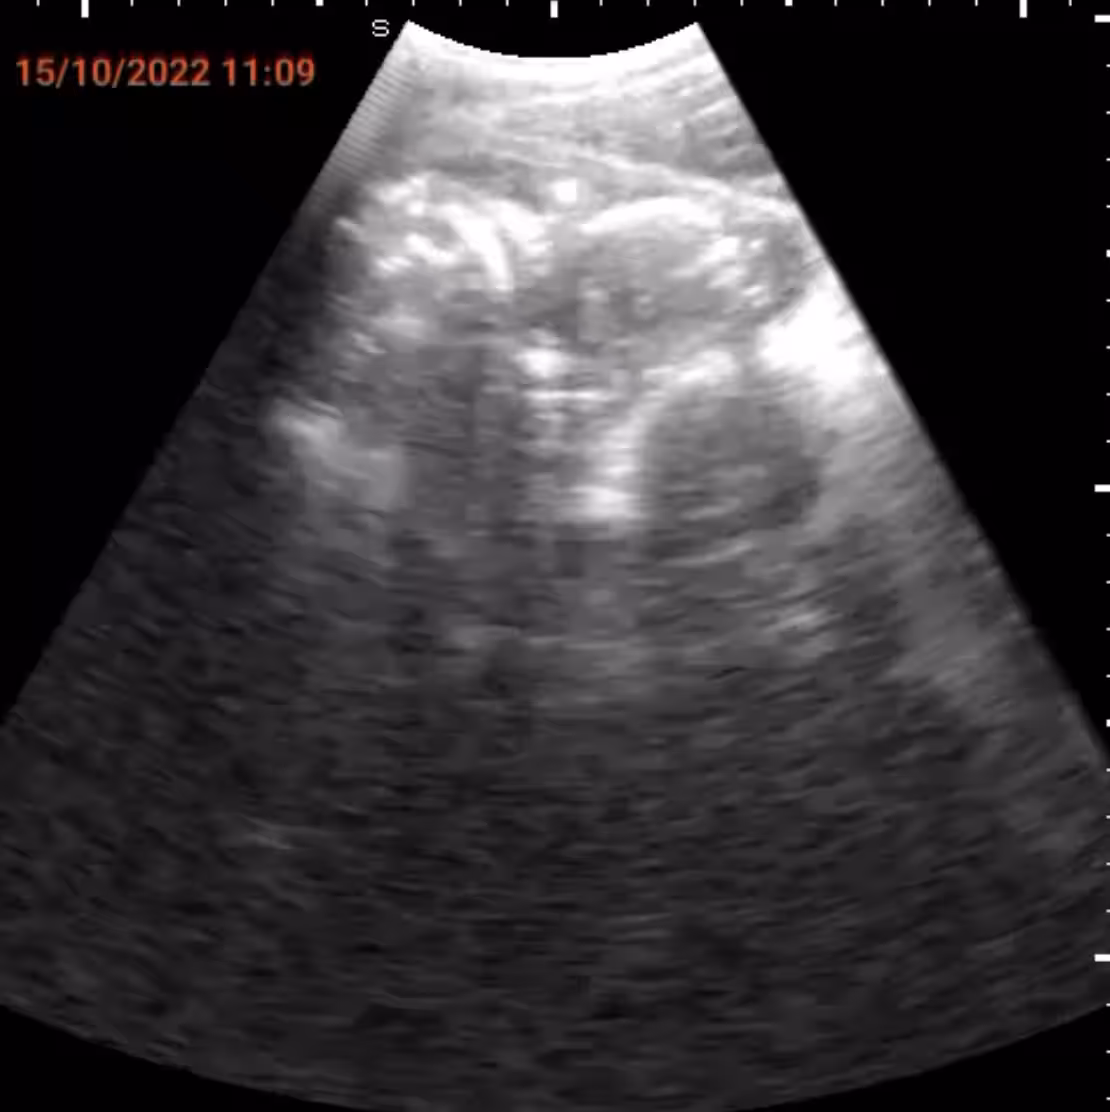

導入予定の「SPAQシステム」は、携帯電話に特別なプローブを接続し、簡便に腹部エコー検査を行える仕組みです。訓練を受けた看護師が現地で妊婦の検診を行い、結果をインターネットを通じて中央病院の医師と共有します。これにより、医師がリアルタイムで診断を行い、緊急時には適切な指示を出すことが可能になるのです。

画像1